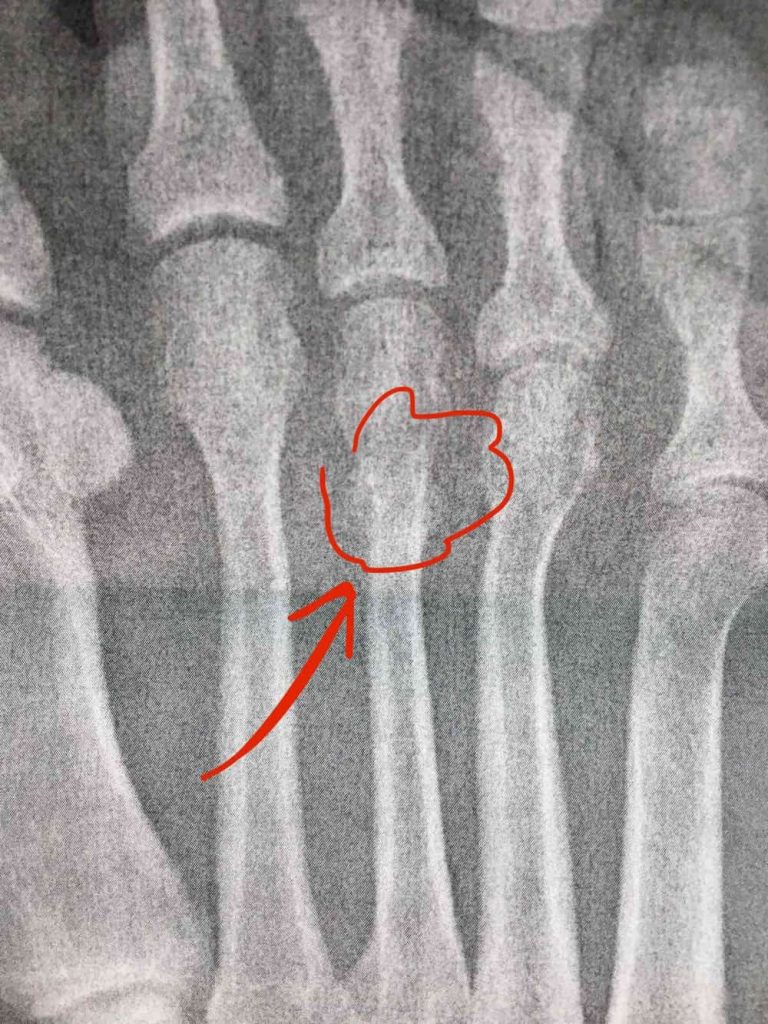

Så med dessa framsteg i bagaget hoppade jag återigen till röntgenavdelningen för vad jag hoppades skulle bli min tredje och sista gång. Vid det här laget ville jag förstås inget hellre än att plåtarna skulle visa på frakturen, vilket i så fall skulle tala om att läkningen var i full gång. Det som röntgenläkaren letar efter kallas för kallus, vilket refererar till den broskliknande vävnad som bildas där en fraktur uppstått när benet är under läkning. Så småningom kommer detta att lösas upp och det hela, rena benet är det enda som återstår. När kallus syns på röntgen innebär det att läkningen kommit långt, men också att en liten bit återstår. Medan jag låg på britsen i röntgensalen råkade jag höra brottstycken av konversationen inne på “kontoret” där de satt och analyserade plåtarna. “Råkade” är givetvis en sanning med modifikation – jag har nog aldrig spetsat mina öron så som jag gjorde då. Hur som helst så tyckte jag mig höra både “kallus” och “tredje metatarsalbenet” och mina förhoppningar sköt omedelbart rakt upp i skyn. Kunde det här vara sant? Kunde det här vara dagen som jag så ivrigt väntat på? Ja, det kunde det – när jag en timme eller så senare träffade ortopeden igen så var jag nära att hoppa upp i hennes famn och ge henne en kyss, eftersom hon i sin hand hade en kopia på röntgenplåten som visade världens snyggaste om än klart suddiga kallus. Efter nio veckors väntande fick jag äntligen min diagnos! Jag trodde aldrig att det skulle göra mig lycklig att få höra en läkare säga “stressfraktur på tredje metatarsalbenet”, men nog fasen gjorde det det. Läkaren rådde mig att pensionera ortosen men att se till att använda stadiga skor de närmaste veckorna, samt avvakta med löpning tills det nya året som en försiktighetsåtgärd. Spinningen var fritt fram att fräsa på med hur hårt jag ville, och egentligen gav hon grönt ljus till allt som inte orsakade direkt smärta. Det här var en sådan lyckans dag för mig, och jag log med hela ansiktet när jag gick ut till Mike i väntrummet, viftandes med röntgenbilden. Jag kunde äntligen se slutet på allting.